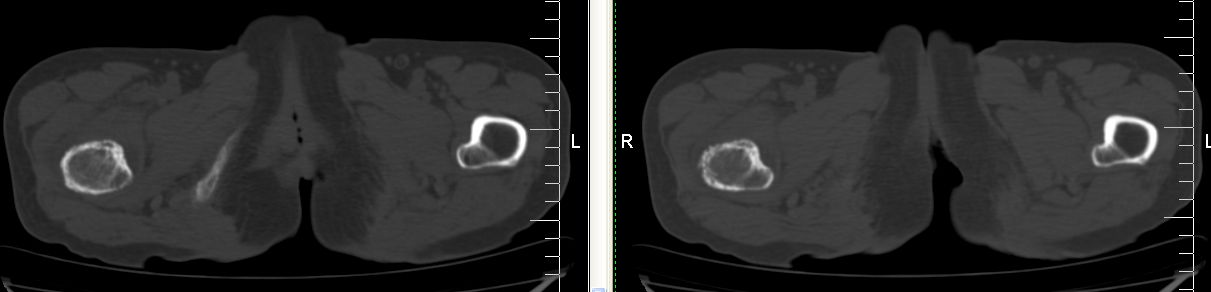

以下是引用余辉在2007-12-5 17:25:00的发言:[br]右侧股骨颈及粗隆区略显膨胀,密度增高略呈不均匀毛玻璃样改变,骨皮质毛糙,考虑1骨纤2骨髓瘤3转移瘤,建议上传软组织窗